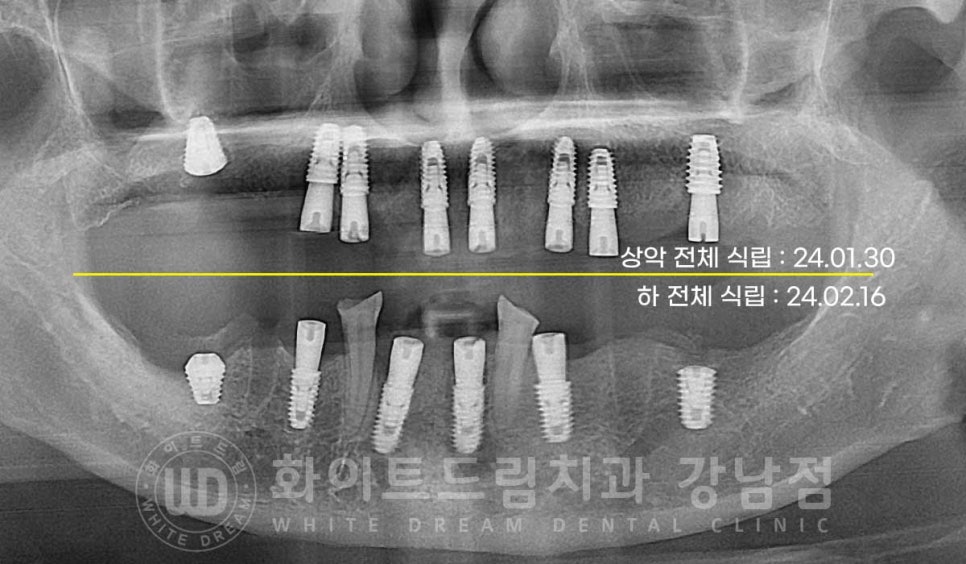

환자분은 멀리 평택에서 내원을 하시는 분이셨기에

내원 당일 상악 전체 → 2주 뒤 하악 전체 식립으로

2회에 걸쳐 전악 임플란트 치료를 진행하기로 했습니다.

그리고 잇몸뼈가 깊숙이까지 염증이 심하게 퍼진 상태는 아니었기에

대부분의 임플란트를 1차 수술과 2차 수술을 동시 진행했고

염증과 골 소실이 심해 많은 양의 뼈이식이 들어간 부위(16번, 46번, 36번)만

1차 수술만 진행하여 잇몸뼈 안에서 잘 자리를 잡을 수 있도록 처치했습니다.

1차 수술은 잇몸뼈 내부에 식립하는 과정을 말하고

2차 수술은 임플란트를 겉으로 노출시키는 과정을 말하는데요.

상/하악 임플란트 식립을 모두 마친 후

이식한 뼛가루가 새로운 뼈로 형성되고, 임플란트가 새로운 뼈와 단단하게 굳는

회복 기간을 거치게 됩니다.

임플란트 회복 기간은 환자분의 치료 전 상태에 따라서 달라지며

빠르면 3개월 길면 6개월까지 기간을 잡고 임플란트의 회복 양상을 지켜보게 됩니다.

환자분은 4개월의 회복 기간을 거친 후 잇몸뼈 안에 매복되어 있던

16,36,46번 임플란트를 겉으로 노출시키는 2차 수술을 진행했고

이후 바로 임플란트 인상채득 & 최종 보철 제작에 들어갔습니다.